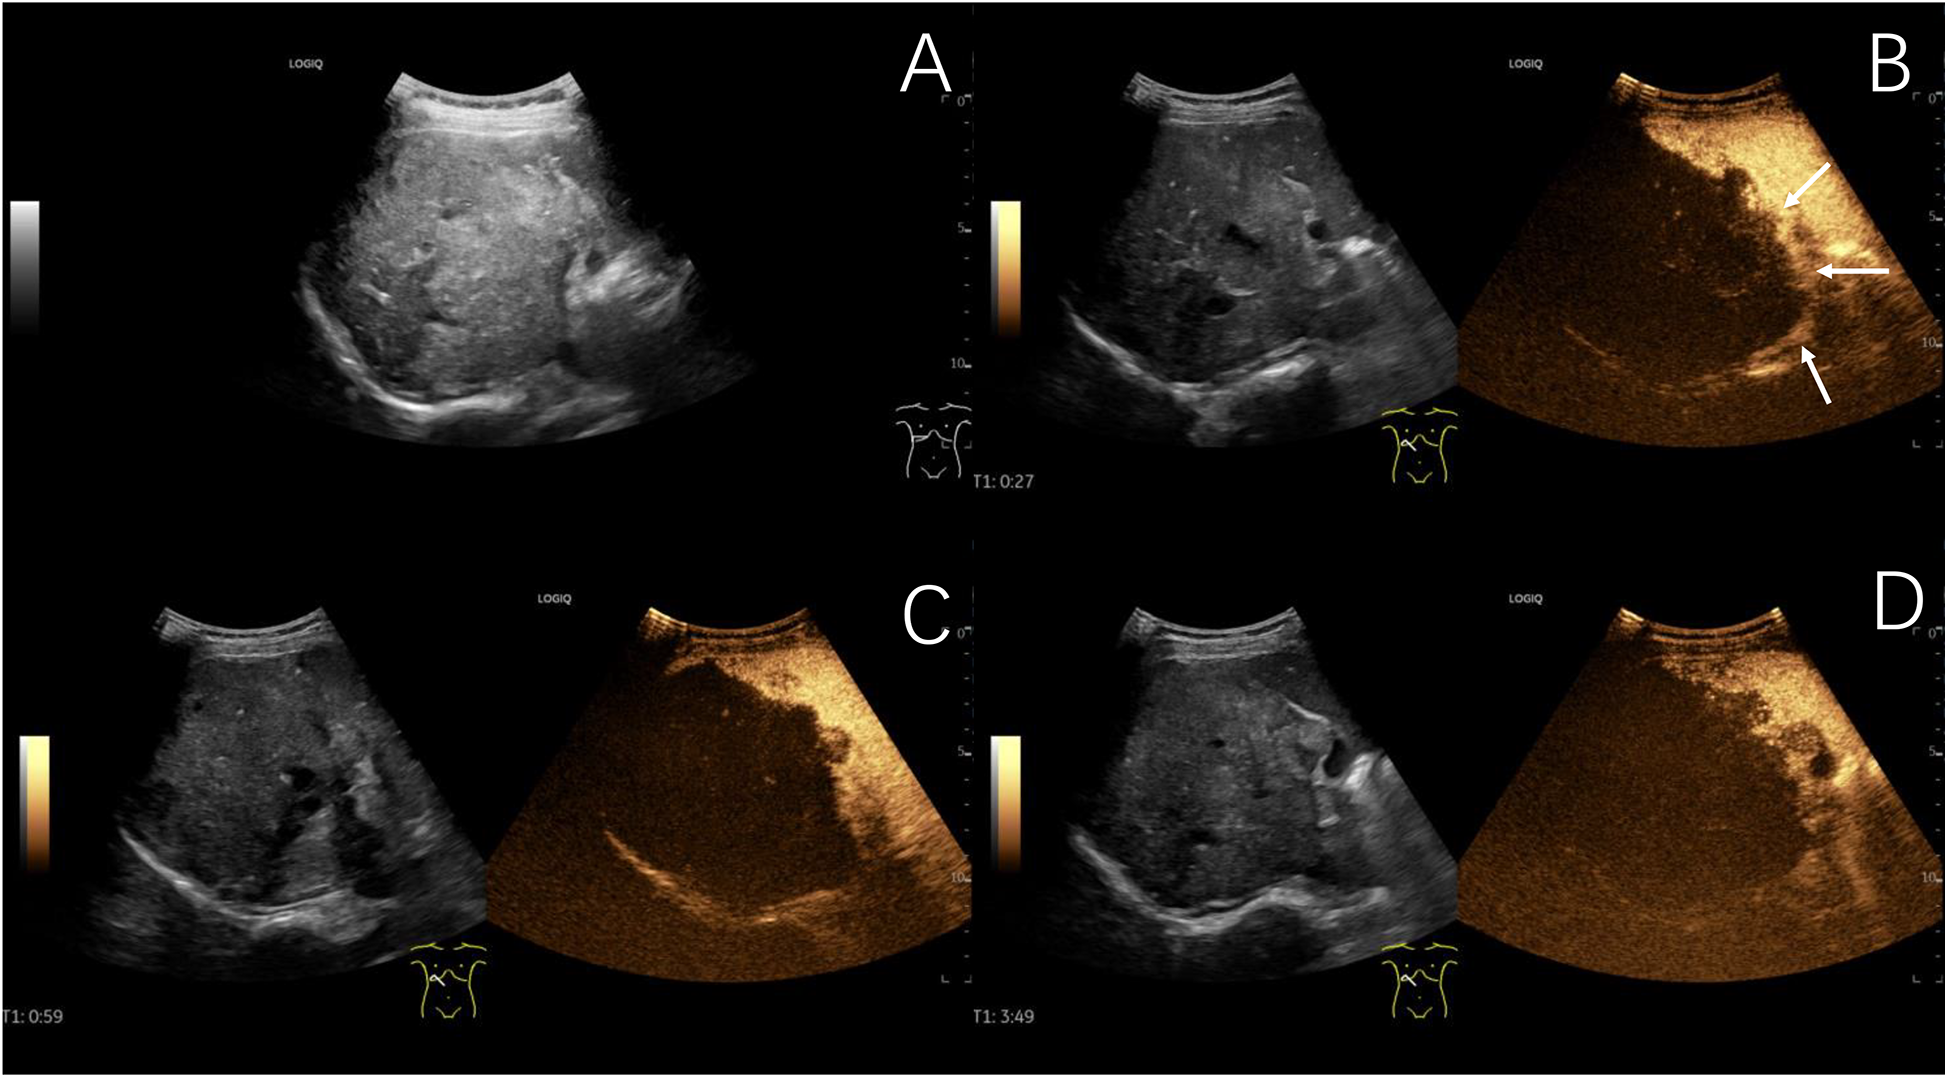

Two out of 31 children of hepatic echinococcosis underwent CEUS. Nine out of 36 children with hepatoblastoma underwent CEUS. One hepatic CE lesion showed no significant enhancement during the arterial, portal venous, and late phases (Figure 2). One hepatic AE lesion showed slight peripheral enhancement during the arterial phase (Figure 3). Nine hepatoblastoma lesions showed hyperenhancement during the arterial phase, six lesions began to washout in the portal venous phase, and nine lesions showed hypoenhancement in the late phase (Figure 4).

Figure 2

www.frontiersin.org

Figure 2. Typical ultrasound findings of hepatic cystic echinococcosis (case 1). Ultrasound of the liver revealed several mixed echogenic masses, with the larger one located in the caudate lobe of the liver, protruding between the left liver and stomach, with a maximum diameter of 127 mm, clear margin, irregular morphology, and patchy strong echoes detected around it (The white arrows show eggshell-like calcification around the lesion) (A) contrast-enhanced ultrasound examination showed no significant enhancement during the arterial phase (B), portal venous phase (C), and late phase (D).